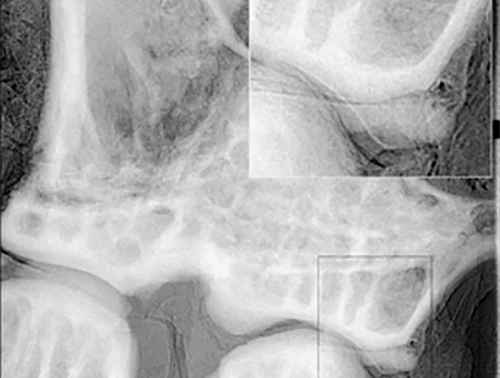

X 射线如何透视体表?

最初是意外发现,X-射线现在在全世界的医疗院所每年被执行约一亿次。这奇妙的“眼睛” 是如何运作 2020-08-31 放射诊疗